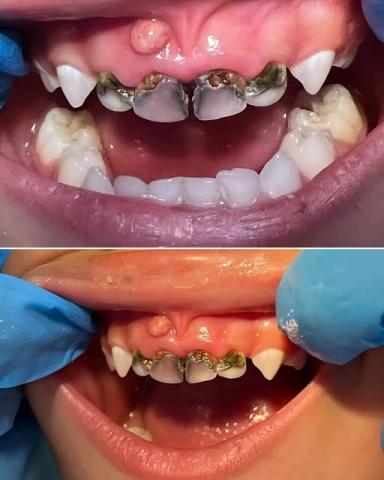

Severe Dental Caries (Tooth Decay) — Multiple upper anterior teeth are extensively decayed with brown to black lesions, indicating advanced enamel and dentin destruction.

Possible Pulp Exposure — The dark central areas likely suggest pulp involvement, explaining the reported pain.

Swollen and Inflamed Gingiva — Noticeable redness and swelling above the upper incisors indicate gum inflammation or infection.

Missing/Partially Erupted Teeth — Several lower teeth show eruption irregularities.

Possible Dental Abscess — The small red bump on the upper gums may indicate a draining abscess (gum boil), suggesting underlying infection.

Rampant Dental Caries

Pulpitis or Early Dental Abscess Formation

Gingivitis or Localized Periodontitis